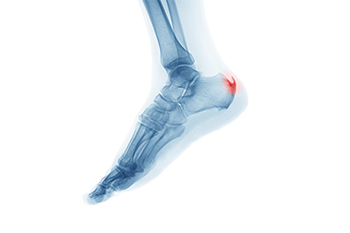

Despite how small a heel spur can be, it is capable of causing severe pain and discomfort. It is defined as a bony protrusion that forms on the bottom of the heel, and can occur due to a heel injury. Additionally, it may occur from overuse while running, and this can cause the heel bone to undergo chronic stress. To compensate for this, the body’s natural defenses will form a bone that protrudes from the heel for protection. Many patients who have heel spurs experience little or no pain, and there are some people who have severe discomfort from a heel spur. This may be a result of an underlying condition that can affect the sole of the foot. An X-ray is often performed that can provide an accurate diagnosis, which can help to determine the severity of the heel spur. Mild relief may be found when lifestyle changes are implemented. These can include losing additional weight, wearing shoes that can accommodate the heel spur and are comfortable, and it may help to limit athletic activities. Surgery may be necessary for permanent relief. If you have developed a heel spur, please confer with a podiatrist who can help you to decide which treatment method is best for you.

Heel spurs are formed by calcium deposits on the back of the foot where the heel is. This can also be caused by small fragments of bone breaking off one section of the foot, attaching onto the back of the foot. Heel spurs can also be bone growth on the back of the foot and may grow in the direction of the arch of the foot.